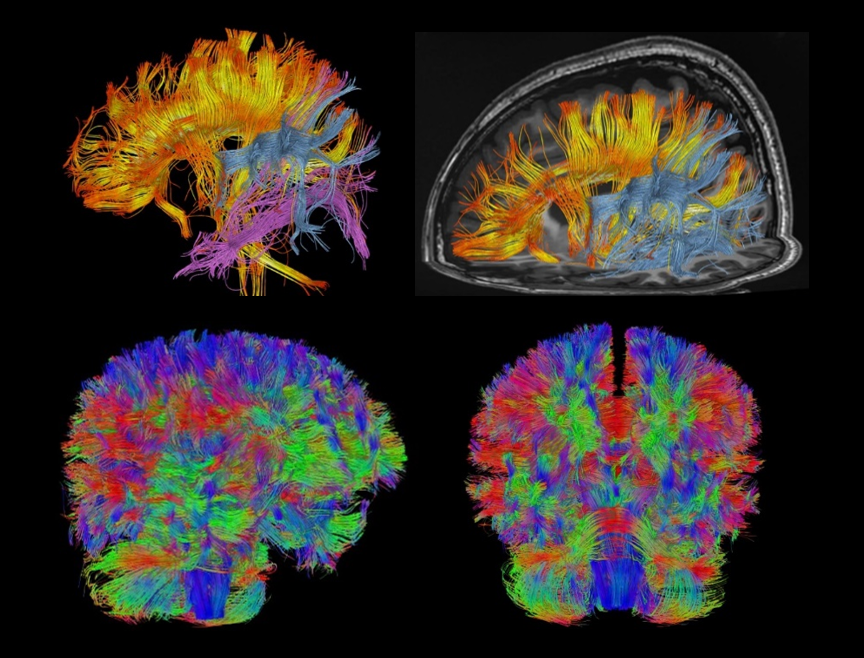

神经系统256方向DTI